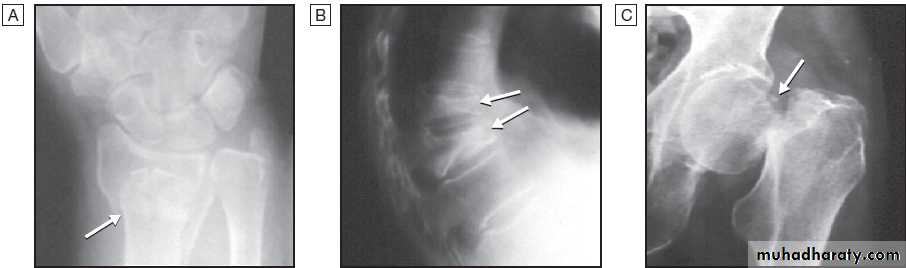

Plain radiographyShow changes of many bone and joint diseases . Radiographs are of diagnostic value in osteoarthritis

X-ray include osteophytes, subchondral sclerosis, bone

cysts and calcified loose bodies within the synovium . Radiographs may show erosions and sclerosis of the sacroiliac joints and syndesmophytes in the spine in seronegative spondyloarthritis. In peripheral joints, so-called proliferative erosions, associated with new bone formation and a periosteal reaction, may be observed.

In tophaceous gout, well-defined punched-out erosions may occur .

Calcification of cartilage, tendons and soft tissues or muscle may occur in chondrocalcinosis , calcific periarthritis and connective tissue diseases. Radiographs are of limited value in the diagnosis of rheumatoid arthritis (RA) since features such as erosions, joint space narrowing and periarticular osteoporosis may only be detectable after several months or even years.Early evidence of articular damage in RA is more usually obtained using MRI or ultrasonography.